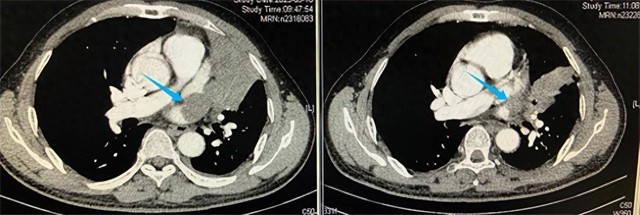

Đỉnh điểm là gần cảm lạnh gần nhất, uống thuốc cả tháng trời cũng không thấy đỡ, cả gia đình thuyết phục mãi chú Nguỵ mới chịu đi khám. Kết quả chụp CT và nội soi phế quản khiến cả nhà choáng váng: trong nửa phổi trên bên phải xuất hiện một khối u khổng lồ, thậm chí đã di căn và "nuốt chửng" một phần tim. Việc phẫu thuật cắt bỏ khối u gần như bất khả thi do kích thước lớn và vị trí nguy hiểm.

Gia đình đưa chú đi thăm khám nhiều nơi nhưng đều nhận kết luận khó phẫu thuật. Tại Bệnh viện Phúc Kiến (Trung Quốc), các bác sĩ đã chọn phương án kết hợp hóa trị và liệu pháp miễn dịch để thu nhỏ khối u trước khi tính tới phẫu thuật. Sau thời gian điều trị, khối u nhỏ lại đáng kể, song ca mổ vẫn tiềm ẩn rủi ro cao. Nhờ kinh nghiệm và kỹ thuật chuyên môn, ê-kíp phẫu thuật đã thành công loại bỏ khối u, nhưng bệnh nhân vẫn cần tiếp tục hóa trị và xạ trị bổ sung, đồng thời đối mặt nguy cơ tái phát.